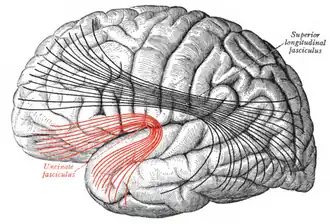

![]() Lateral surface of left cerebral hemisphere. Some of the major association tracts are depicted. Uncinate fasciculus is at lower left, in red. | |

Diagram showing principal systems of association fibers in the cerebrum. (Uncinate fasc. visible at lower left, in red.) -